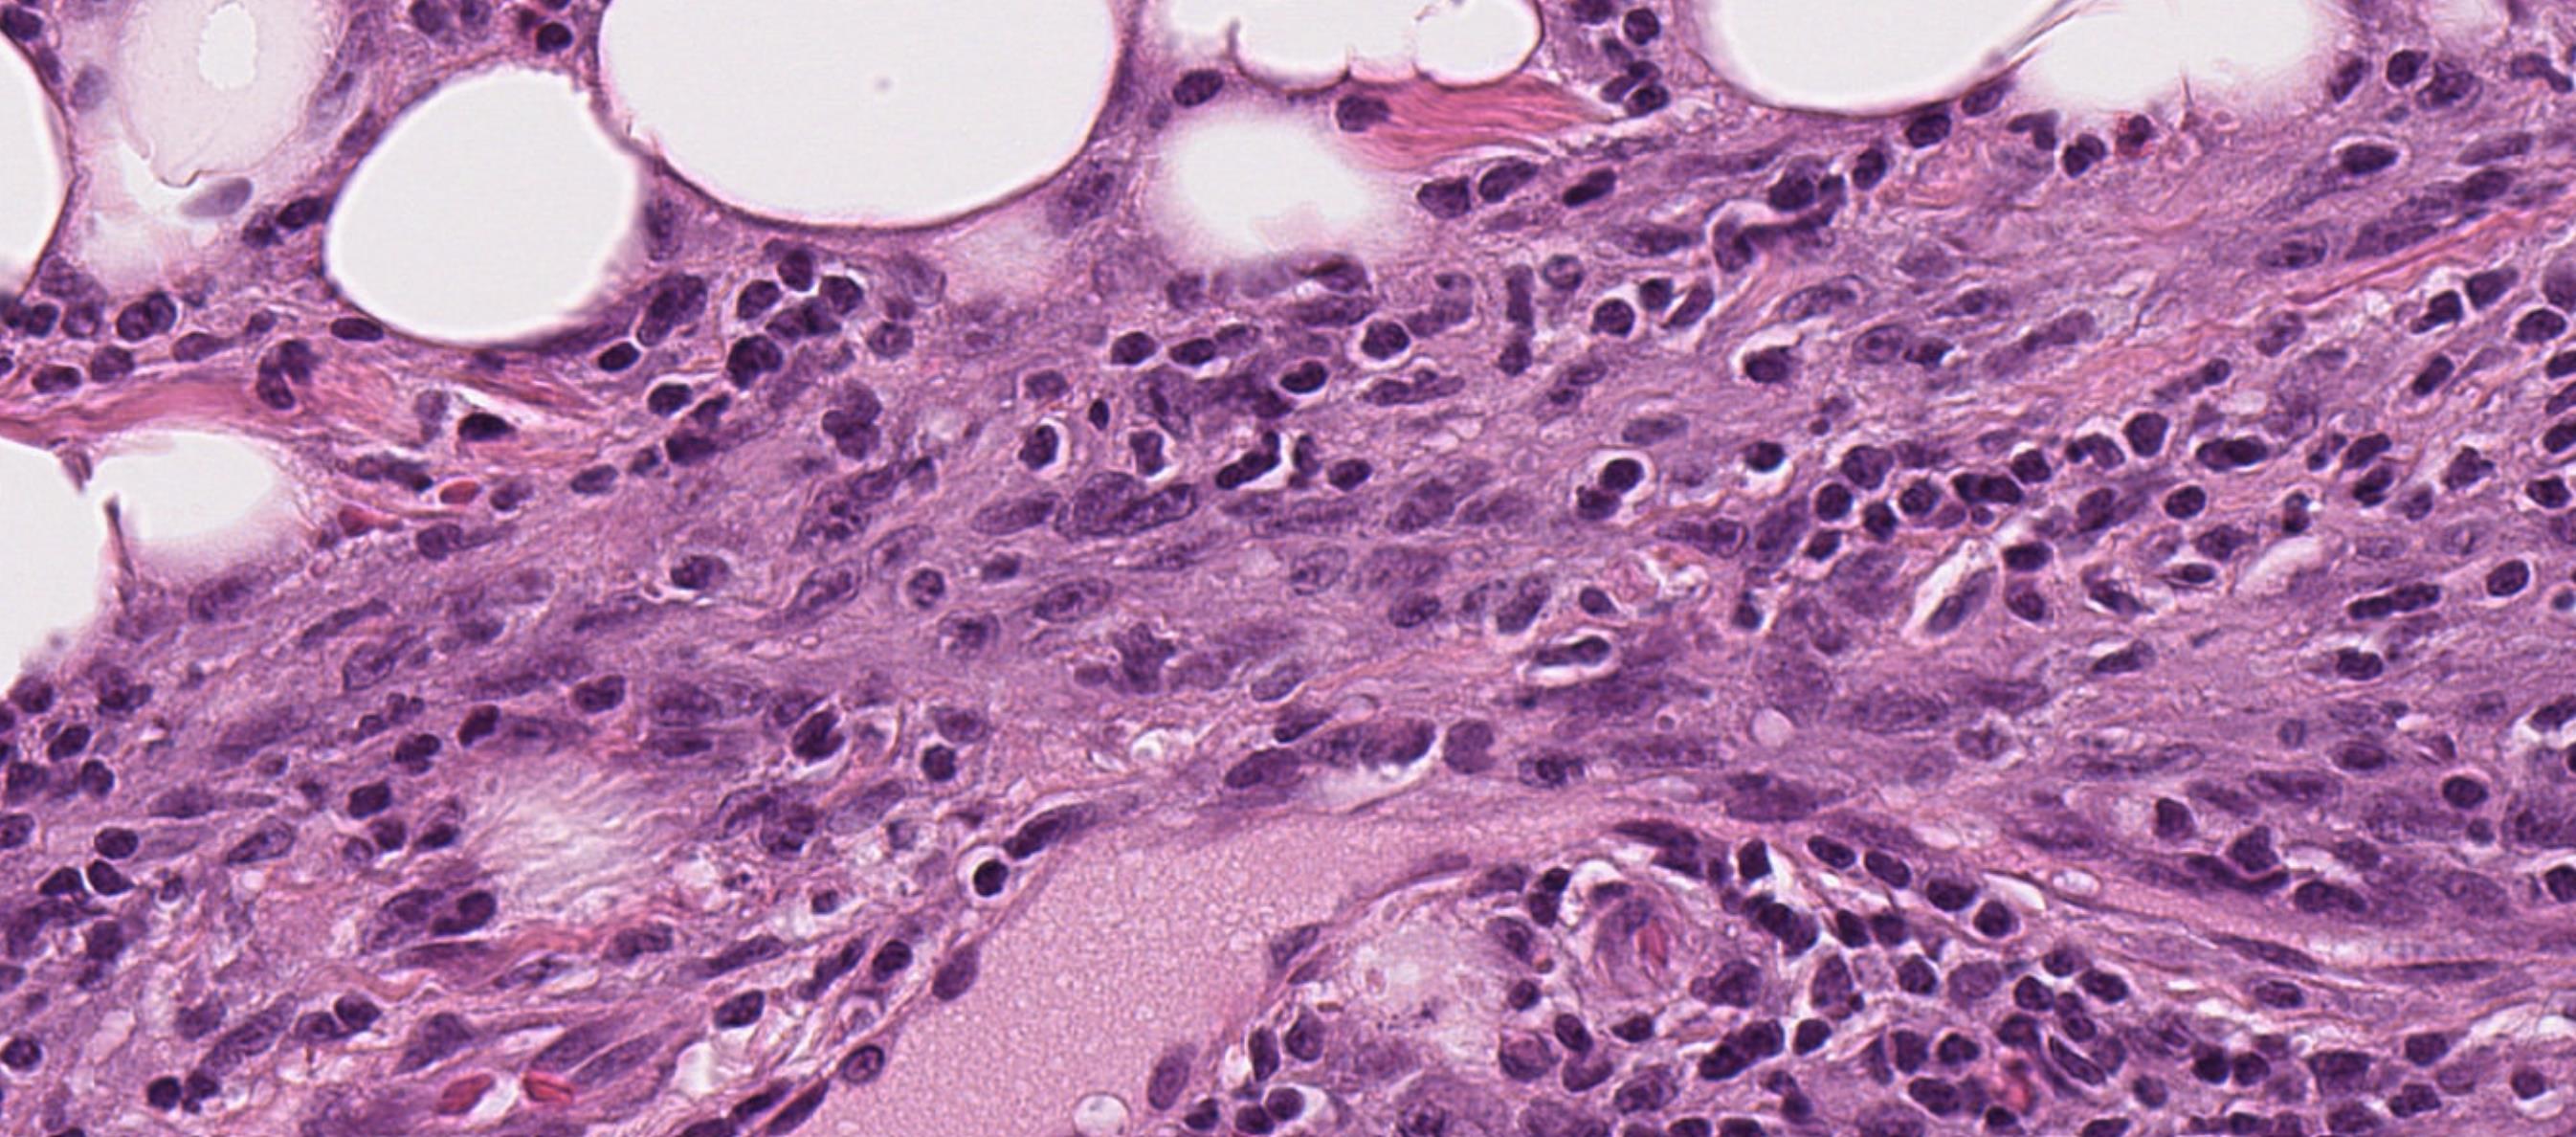

55-year-old Male, Large thyroid mass.

Salient points • Papillary carcinoma component • Spindle cell component • 4 possibilities for the spindle cells • Spindle cell metaplasia of follicular cells- epithelial (bland cytology) • Fibromatosis/fasciitis like spindle cell stroma- fibrous (bland cytology) • Anaplastic transformation of PTC (rare) –HG cytology • Sarcomatous transformation of PTC (very rare)- HG cytology How to make the distinction? IHC Molecular –ATC: B catenin, TP53

Case 3 Diagnosis

Papillary thyroid carcinoma with sarcomatous differentiation